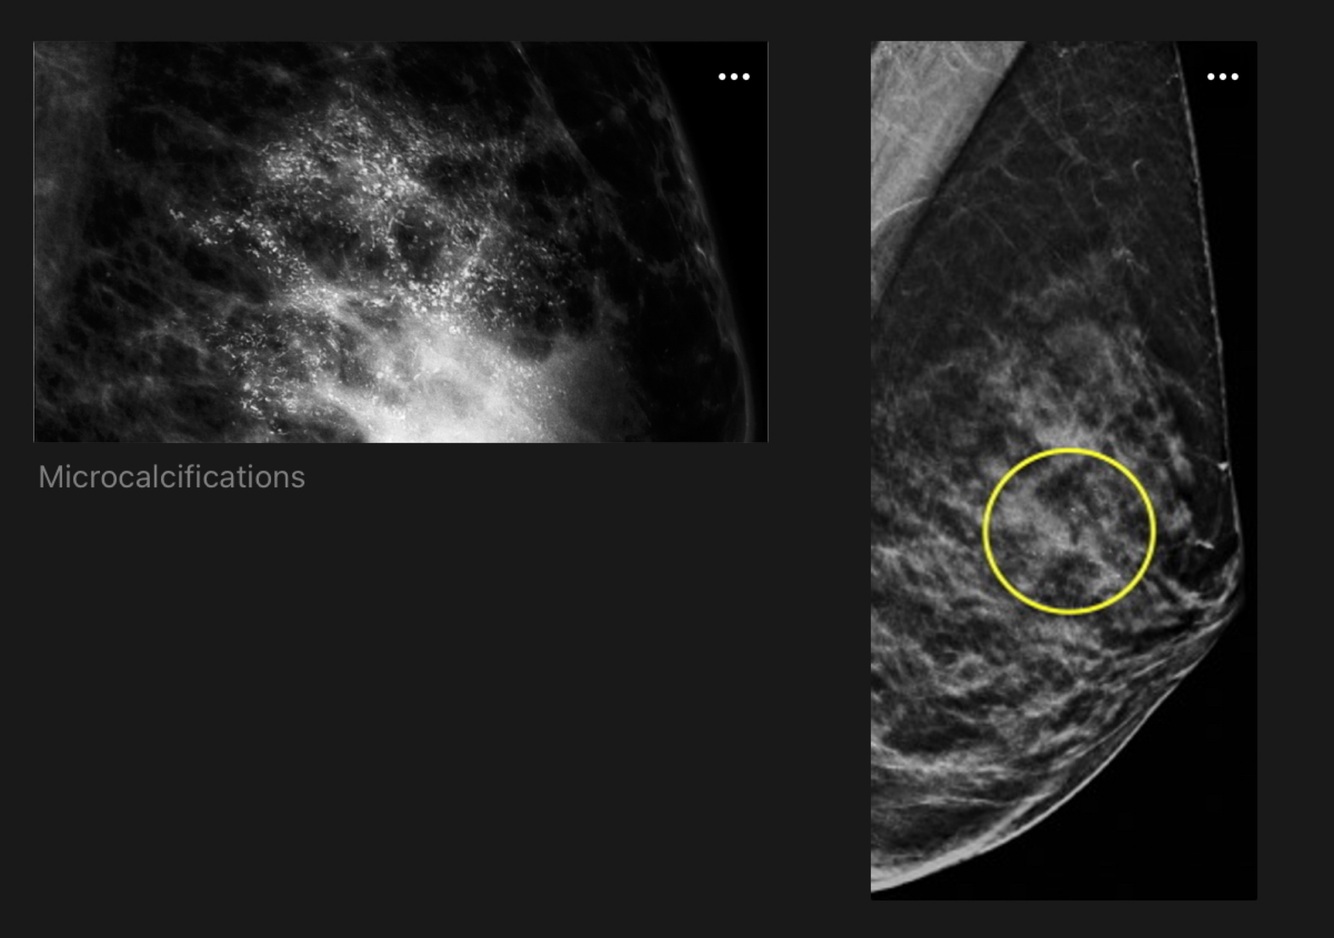

MMG

- Patients with suspected DCIS should have a diagnostic bilateral mammogram with magnification views to assess the morphology and full extent of any calcifications.

- 70% have microcalcifications without mass

- 30% have microcalcifications with mass on MMG

- 10% patient has mass, density or architectural distortion without calcification

- Usually Multifocal: widespread calcification with extension along mammary ducts towards the nipple.

- Low grade DCIS: Fine, granular calcification.

- High grade DCIS: Coarse granular calcification, linear branching.